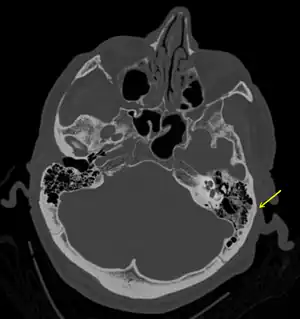

A subtle temporal bone fracture as seen on CT in a person with a severe head injury

Basilar skull fractures include breaks in the posterior skull base or anterior skull base. The former involve the occipital bone, temporal bone, and portions of the sphenoid bone; the latter, superior portions of the sphenoid and ethmoid bones. The temporal bone fracture is encountered in 75% of all basilar skull fractures and may be longitudinal, transverse or mixed, depending on the course of the fracture line in relation to the longitudinal axis of the pyramid.[6]